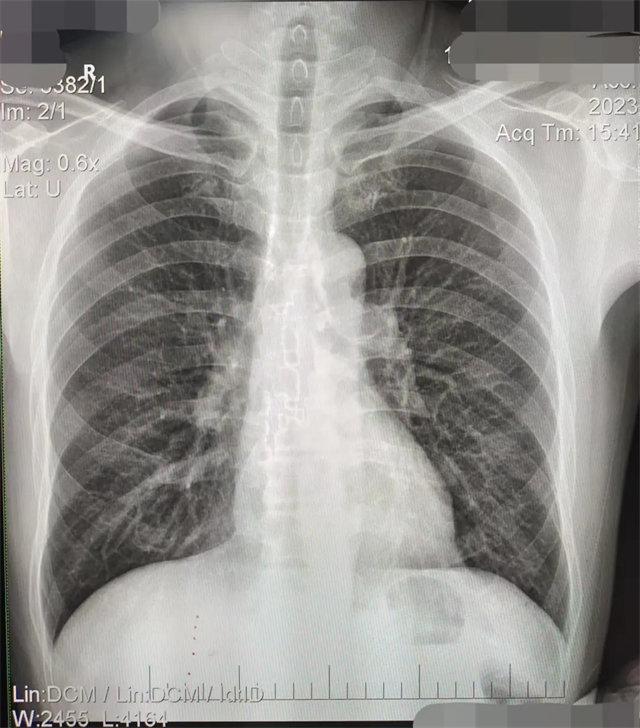

缺陷:肩胛骨未完全拉离肺野,吸气不完全,存在金属伪影遮挡,略有耸肩,且肺尖显示不好,图像颗粒感较强,管电流量不够,信噪比偏低。

解决:去除金属物品后,按标准体位,使患者双肩旋前与前胸一并紧贴成像件,适当调高mAs,然后深吸气后屏气曝光。